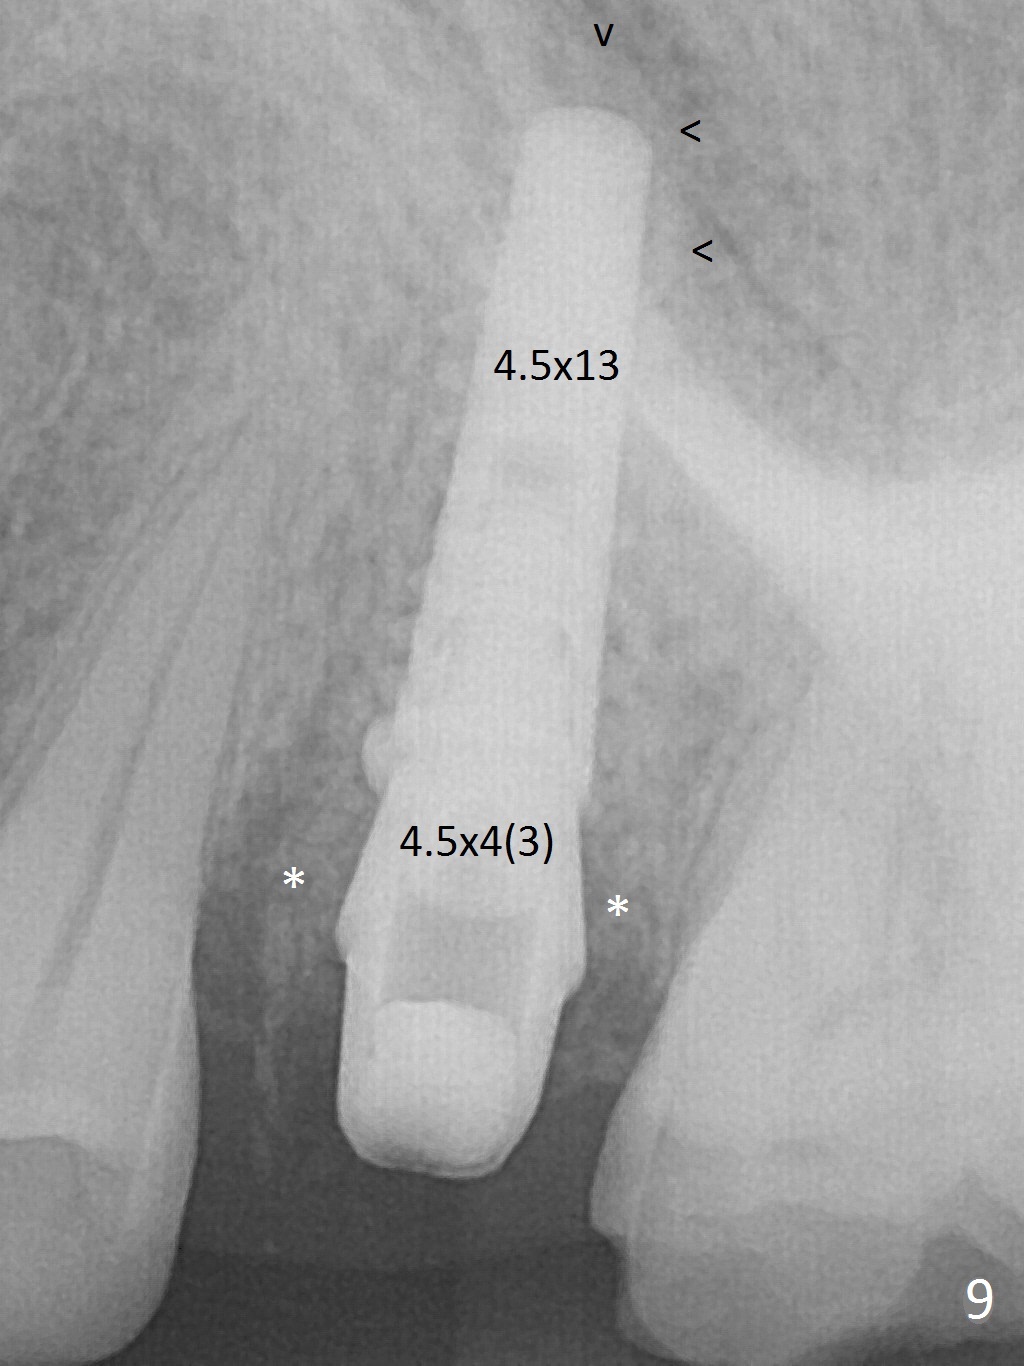

The buccal gingiva over the tooth #13 (Fig.1 white *) with crack (Fig.2 (mesial view of the extracted tooth)) is erythematous with deep buccal (B) pockets, which do not appear to extend the level of exostosis of the neighboring teeth (Fig.1 black *), i.e., coronal to the apical end of the crack with granulation tissue (Fig.2 *). Osteotomy is initiated with a 1.6 mm drill in the palatal aspect of the socket (Fig.3) so that an implant will be placed palatal (Fig.8,11) and there is enough buccal gap for bone graft (Fig.8 *). After withdrawal of 3.3 mm Magic Drill (trephine bur), the osteotomy (Fig.4 O) plug (red outline) is intentionally left in situ. When a 4x11 mm dummy implant is placed (Fig.5 (green outline), 6), the plug is compressed (Fig.5). With placement of a definitive implant (4.5x13 mm, Fig.7 (green), 9), the plug as well as the sinus floor (Fig.4 SF) is lifted (Fig.7 red curved line), 9 (arrowheads)). In brief the autogenous bone is used for sinus lift. There is no intra- or post-op nasal hemorrhage. With a small piece of gauze (Fig.8 G) in the implant well, allograft is placed in the buccal (mainly) and palatal gaps until the level of the implant plateau. Then a 4.5x4(3) mm abutment is placed (Fig.9-10 A). Next another piece of gauze is placed in the space corresponding to the abutment cuff (Fig.11 G) for fabrication of an immediate provisional (Fig.12 P). More bone graft is placed in the soft tissue zone (dual zone technique) after gauze removal and before provisional seating. With dual zone bone graft technique and provisional support, the soft tissue atrophy should be expected to be minimal (Fig.12 *). The zone of exostosis (more coronal) should be much less, since the bone density in the zone is high.

The buccal gingival inflammation subsides 1 week postop (Fig.13,14). There is no bone loss 4 months postop (Fig.15,16). The crown is recemented 6 months post cementation (probably due to short abutment); there is a residual cement (Fig.17 <), which is removed (Fig.18).